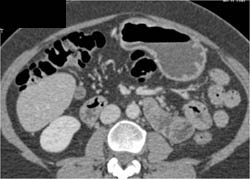

Diagnosis

Antral Cancer